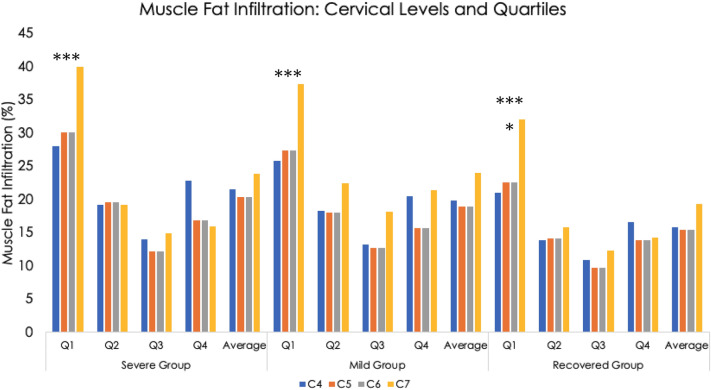

For all three groups, the most medial quartile, Q1, had the highest level of MFI (p < 0.001, see Fig. 4). For all four cervical levels (C4 through C7), the recovered group had significantly less MFI in Q1 compared to the symptomatic groups (p < 0.05). This was also found for the second-most medial quartile, Q2, at levels C4 and C5 (p < 0.05). Group differences were not found in the more lateral quartiles, Q3 and Q4 at any level (C4 through C7). There was a trend towards a significant group * quartile interaction effect at the cervical level, C5 (p = 0.05).

Figure 4.

Muscle fat infiltration by group, Cervical level (C4–C7, Quartiles (Q1–Q4), and average of the all Quartiles*Level.

Consistent with preliminary work1,7, MFI appears to be equally distributed between the more lateral quartiles at all levels analysed (C4-C7) and across all groups, but, once again, Q1 contains the highest MFI levels with significantly larger magnitudes in the two symptomatic groups compared to the recovered group. This provides supportive data mapping the spatial distribution and magnitude of MFI in the deep extensor muscles in a larger sample of individuals with varying levels of WAD-related disability at one-year post injury when compared to preliminary quantitative1 and qualitative7 reports.